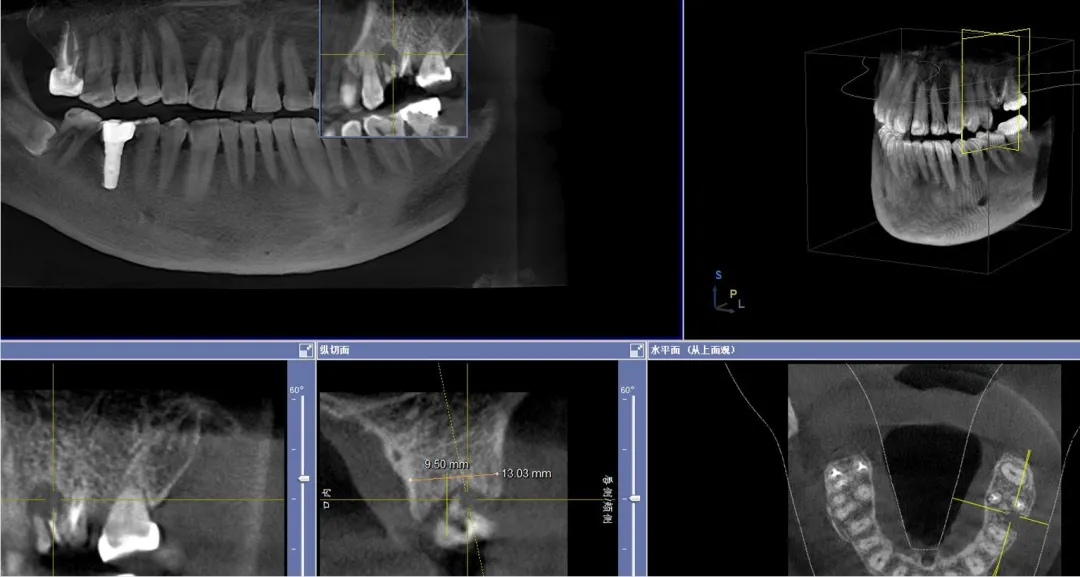

病例分享:患者男,诊断左上六慢性根尖炎劈裂;处置:基础治疗+即刻种植(种植前中后进行光动力疗法照射1min(2次)